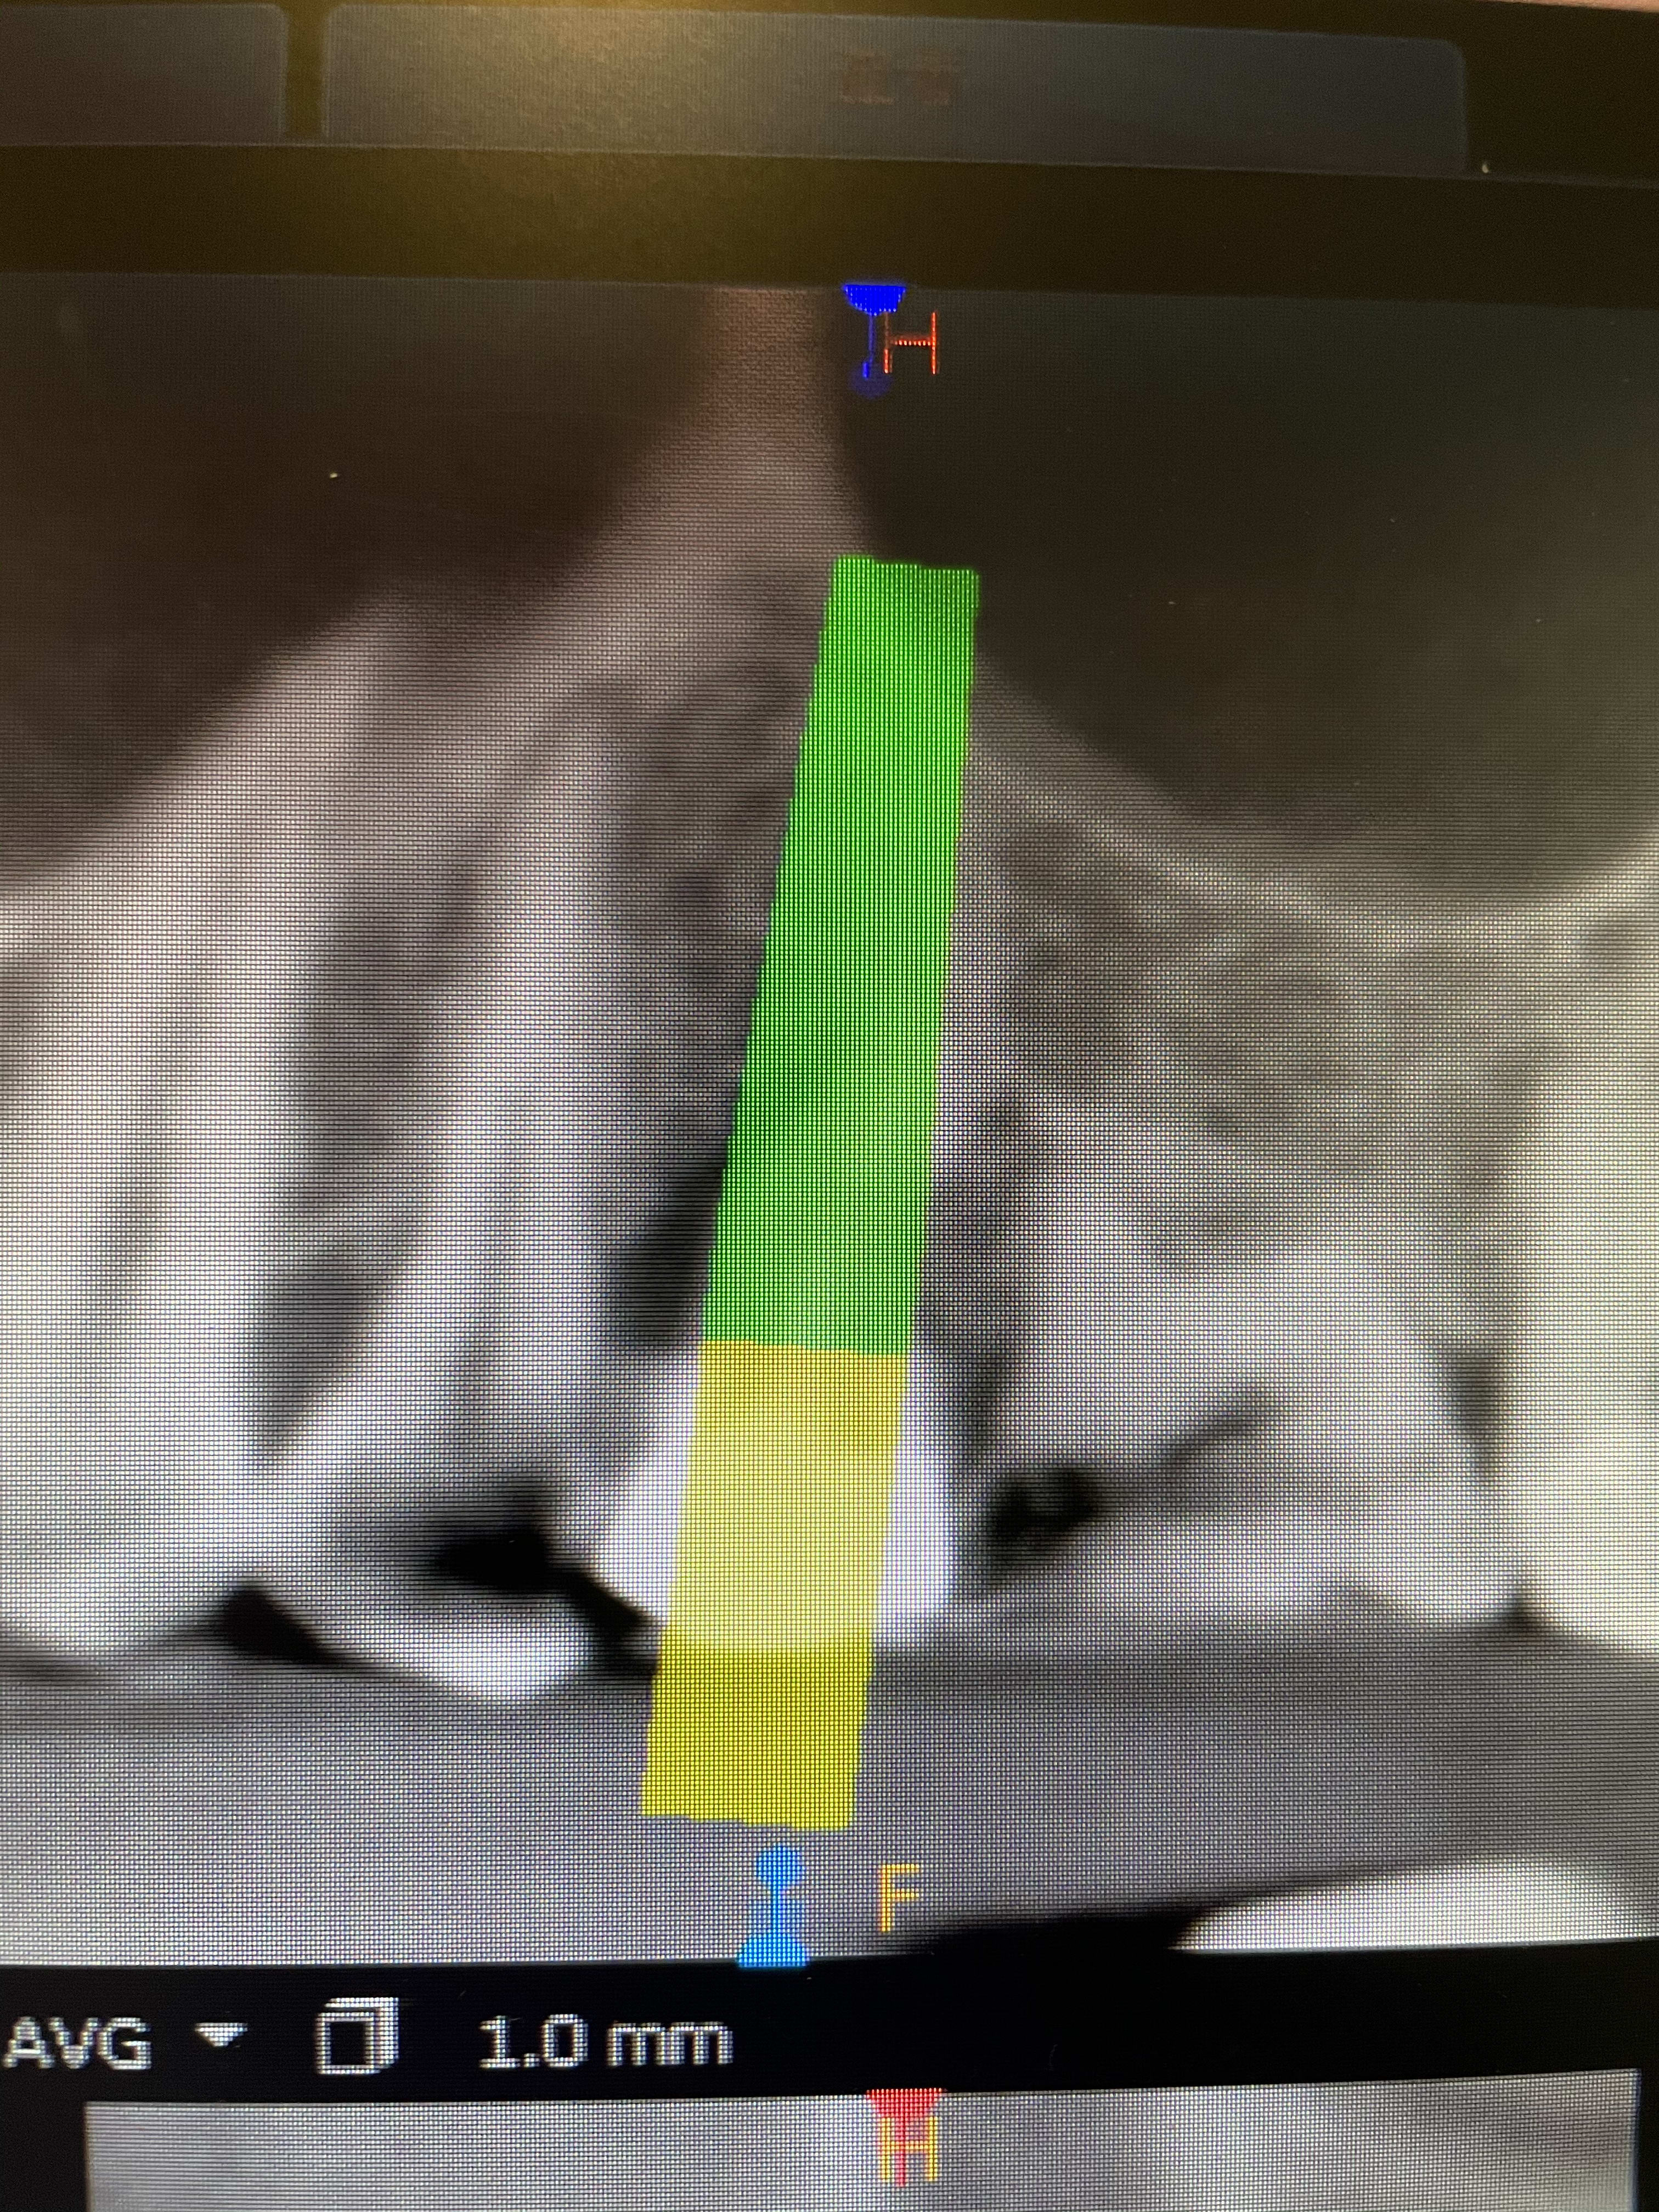

Forage, je franchis la corticale sinusienne avec le premier forêt, pas avec les autres.

Vissage d’un dentium superline SLA en 4x14mm bloqué à 30N.cm, je monte à 55.

D’où l’intérêt d’utiliser la corticale, la perforation est contrôlée, seul le foret le plus fin a percé la corticale sans percer la membrane (j’espère) ensuite au vissage la corticale et la membrane sont gentiment soulevées.

Dans ce cas l’implant est très long, mais je le fais très souvent, ça permet de gagner 2mm de hauteur facilement sans faire un summers. Typiquement avec 8mm de hauteur je mets un 10mm, ou un 8 avec 6mm de hauteur c’est très courant. Jamais eu de problème sur des dizaines de cas.